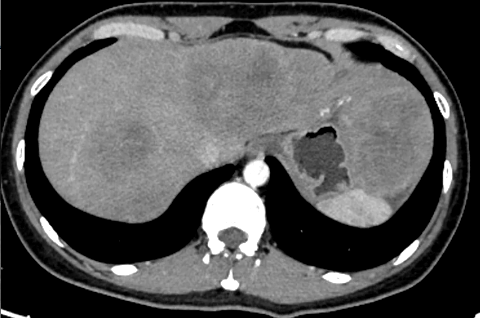

实验室检查:CEA 4289ng/ml,CA242 488.4U/ml,CA199 529.9ng/ml;AST 133.6U/L,ALT 88.7 U/L全腹平扫+增强CT提示肝脏多发占位性病变,直肠上段壁增厚,边缘毛糙,不均匀强化,周围见多发肿大淋巴结(图2)。

直肠中分化腺癌伴多发肝转移(IVA期, cTxN+M1a)。